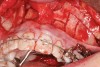

Fig 4. Note gingival inflammation caused by biologic width violation. Provisional restorations were placed on Nos. 6, 8, 9, and 11, and corticotomies were performed from Nos. 3 to 14.

Figure 4

Fig 10. A corticotomy in SFOT is a surgical technique in which only the cortical bone is cut, perforated, or mechanically altered to the depth of the medullary bone and the medullary bone remains intact.

Figure 10